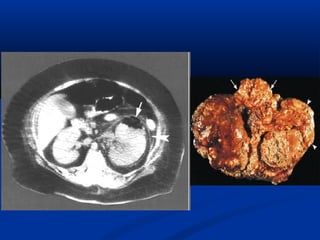

Vieâm thaän – beå thaänVieâm thaän – beå thaän

haït vaønghaït vaøng

- Beänh nhieãm truøng sinhBeänh nhieãm truøng sinh

muû maïn tính cuûa thaänmuû maïn tính cuûa thaän

laøm huûy hoaïi chuû moâ,laøm huûy hoaïi chuû moâ,

thay vaøo caùc ñaïi thöïcthay vaøo caùc ñaïi thöïc

baøo chöùa ñaày caùc haïtbaøo chöùa ñaày caùc haït

lipid.lipid.

- Thöôøng ñi keøm soûiThöôøng ñi keøm soûi

thaän vaø beänh thaän taécthaän vaø beänh thaän taéc

ngheõn.ngheõn.

- Gaëp ôû phuï nöõ trung nieân, ngöôøiGaëp ôû phuï nöõ trung nieân, ngöôøi

tieåu ñöôøngtieåu ñöôøng

- Laâm saøng khoâng ñaëc hieäu, ñau,Laâm saøng khoâng ñaëc hieäu, ñau,

khoái u, suït caân, nhieãm truøng tieåu…khoái u, suït caân, nhieãm truøng tieåu…

- Thöôøng xaûy ra moät beân, lan toûa,Thöôøng xaûy ra moät beân, lan toûa,

töøng vuøng hoaëc khu truù.töøng vuøng hoaëc khu truù.

 Sieâu aâm:Sieâu aâm:

• Theå lan toûa:Theå lan toûa:

• - Thaän phì ñaïi, giöõ nguyeân hình daïng, maát phaân bieät voû- Thaän phì ñaïi, giöõ nguyeân hình daïng, maát phaân bieät voû

– tuûy.– tuûy.

• - Nhieàu vuøng giaûm phaûn aâm töông öùng ñaøi thaän bò- Nhieàu vuøng giaûm phaûn aâm töông öùng ñaøi thaän bò

giaõn nôû hoaëc vuøng nhu moâ bò vieâmgiaõn nôû hoaëc vuøng nhu moâ bò vieâm

• - Ñoä thaáu aâm thay ñoåi theo möùc ñoä hoaù loûng cuûa caùc- Ñoä thaáu aâm thay ñoåi theo möùc ñoä hoaù loûng cuûa caùc

khoái nhu moâ.khoái nhu moâ.

• - Xoang thaän trung taâm coù theå taêng phaûn aâm roõ reät- Xoang thaän trung taâm coù theå taêng phaûn aâm roõ reät

keøm boùng löng töông öùng vôùi soûi san hoâ lôùn.keøm boùng löng töông öùng vôùi soûi san hoâ lôùn.